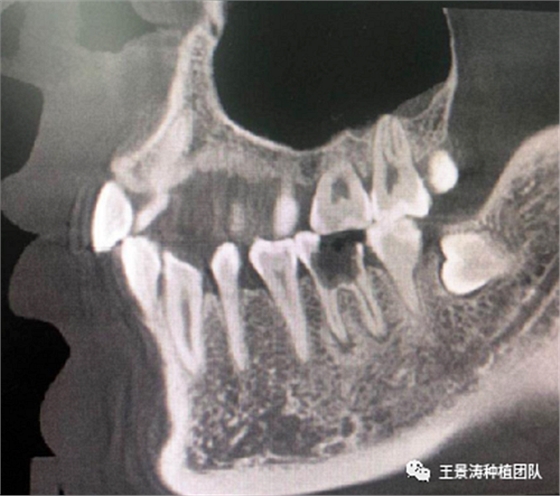

下述病例則是15區(qū)域的即刻種植,15因牙冠折斷于齦下,無法樁核冠修復(fù),則考慮種植修復(fù)。但拍攝CBCT后發(fā)現(xiàn)根尖距上頜竇底距離較短。患者為年輕女性,無全身系統(tǒng)疾病且可利用上頜竇底與根尖皮質(zhì)骨雙側(cè)皮質(zhì)骨固位,且此位置可通過頰側(cè)軟組織減張技術(shù)獲得嚴(yán)密封閉牙槽窩。因其根尖距上頜竇距離較低,遂拔除15后行上頜竇內(nèi)提升,埋入式種植,最終修復(fù)的完成。

左側(cè)下頜第二磨牙及右側(cè)下頜第一磨牙同時(shí)即刻種植病例?;颊吣贻p女性,無系統(tǒng)性疾病。37及46殘冠及殘根,且46劈裂,無法冠修復(fù),必須拔除。37根尖慢性炎癥,大量肉芽組織存在,46根分叉較高,根分叉骨質(zhì)尚可。CBCT示:根尖骨質(zhì)至下牙槽神經(jīng)管距離可滿足種植體的初期穩(wěn)定性,遂考慮即刻種植,并在種植體周邊填入骨粉并覆蓋骨膜,雙側(cè)的種植體初期穩(wěn)定性相差無幾,但考慮到37根尖慢性炎癥較大,遂給予埋入式種植。